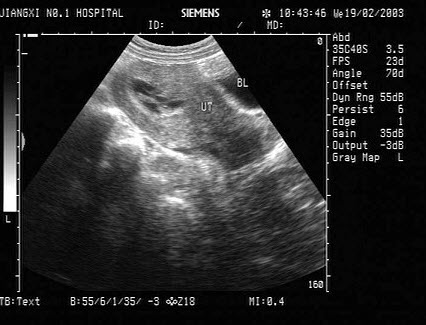

2、单项选择题

下图为宫内孕囊声像图,可见心管搏动,该胎儿至少大于多少周()

A.6周

B.9周

C.10周

D.12周

E.8周